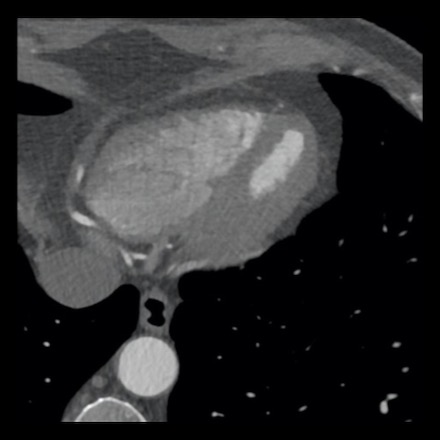

case 1 – CAD-RADS 2/P1

First, scroll through the scan.

Not all images are included. Some images without any abnormalities are skipped

from the series.

How would you describe the findings on the coronary CTA?